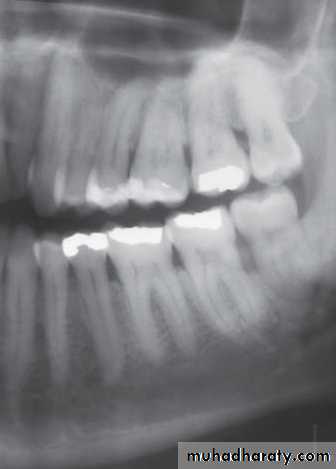

Radiographic features:* Soft tissue inflammation→no change. Location: Most common site → mand 3rd molar region.

*In close proximity to bone or inside follicular space.

*Radiolucency or sclerotic with thick trabeculae.

Periphery: ill defined with gradual merging with sclerotic region.Internal structure: *Sclerotic with thick trabeculae. Or radiolucency adjacent to crown.

Effect on surrounding structures:*Sclerosis and rarefaction of surrounding bone.

*In extensive cases, new bone formation at inferior cortex, posterior border of the ramus, and

along the coronoid notch.